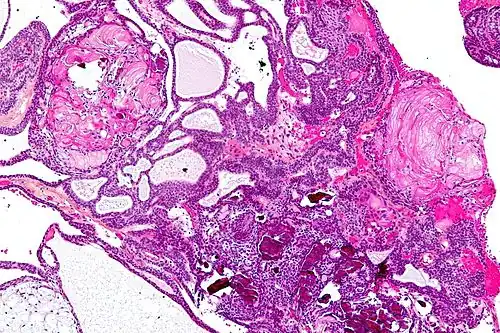

| Very low magnification micrograph of an adamantinomatous craniopharyngioma. HPS stain. | |

Micrograph showing the characteristic features of an adamantinomatous craniopharyngioma - cystic spaces, calcifications, and "wet" keratin, HPS stain -

On macroscopic examination, craniopharyngiomas are cystic or partially cystic with solid areas. On light microscopy, the cysts are seen to be lined by stratified squamous epithelium. Keratin pearls may also be seen. The cysts are usually filled with a yellow, viscous fluid rich in cholesterol crystals. Of a long list of possible symptoms, the most common presentations include headaches, growth failure, and bitemporal hemianopsia.